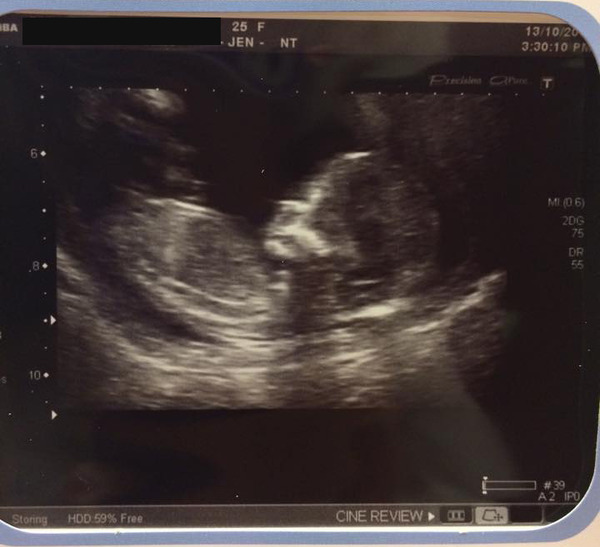

Scan went really well. Two arms, two legs attached to a wriggly baby Grin

The sonographer put me back AGAIN though, even though I know that's not possible as I know the day we dtd. She said the dates can be a bit off with baby curled up and because it's harder to measure with my tilted uterus. Ah well, she put me at 12+4 and EDD 23rd April.

Nuchal measurement was good, 1.7mm. Just have to wait for bloods now. Fingers crossed that's all good. Next scan is not until 8th December though, seems SO far away!

Ahhh, what a beautiful scan pic, lady

Scan went well today, only a 30min wait, and there's only one in there, phew!! Chuffed as I've gained 4 days so I've moved forward to 12+4 so same as you now LadyNovember (ps lovely pic!) NT looked good so just need to wait for blood results.

fizzybubbly your scan picture is amazing! You can see everything so clearly. Bet you're well chuffed with it.

Lady and Fizzy, beautiful scans!